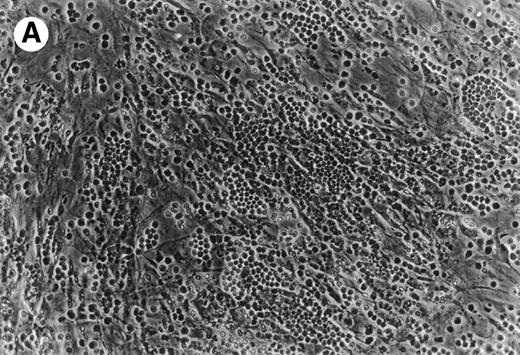

CLL B cells migrate beneath heterologous MSC (Pseudoemperipolesis).

Coculture of CLL cells with the murine-marrow-stroma cell-line, M2-10B4, results in spontaneous migration of CLL cells into the stromal cell layer. This in vitro phenomenon termed pseudoemperipolesis is characterized by the dark appearance of cells that have migrated into the same focal plane as the stromal cells, whereas the more superficial, nonmigrated cells remain refractile (Fig 6).30 Time-course experiments showed that pseudoemperipolesis of CLL cells mostly occurred within the first 2 hours of coculture (Fig 7B). Titration of the input CLL cell numbers showed that concentrations above 1 × 107 cells per 24 well plate did not significantly increase the number of migrated cells (Fig 7C). A 2-hour assay with 1 × 107 input cells was found to be the optimal condition for this assay and hence was used in subsequent inhibition studies. Under these conditions, an average of 7.4% ± 3.7% (mean ± SD) of input CLL cells from 6 different patients migrated into the stromal layer. For comparison, we assessed the migration of Nalm-6 cells and found that 6.9% ± 0.5% (mean ± SE of duplicate tests) of the input cells migrated into the stromal layer under the same experimental conditions.

(A) Representative phase contrast photomicrograph of pseudoemperipolesis of CLL B cells after 2-hour culture on the heterologous murine stromal cell line, M2-10B4. Cells that had not migrated beneath the stromal cells washed off, and the stromal cell layer containing the migrated CLL cells was photographed (200x magnification). Pseudoemperipolesis is characterized by the dark appearance of lymphocytes that have migrated into the same focal plane as the stromal cells. (B) For comparison, this photomicrograph shows reduced pseudoemperipolesis after pretreatment of CLL cells with pertussis toxin.